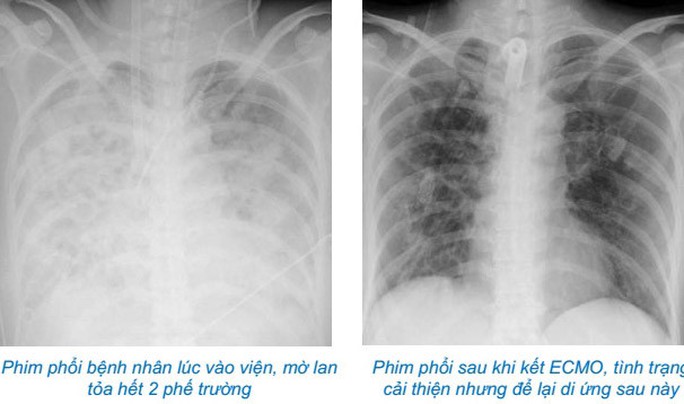

Là bác sĩ trực tiếp điều trị cho bệnh nhân, ThS.BS Nguyễn Bá Cường - Trung tâm Hồi sức tích cực, Bệnh viện Bạch Mai chia sẻ trên VTC News, khi vào trung tâm, tình trạng bệnh nhân rất nặng nề, sốt cao liên tục, sốc nhiễm khuẩn nặng, oxy máu giảm rất thấp, X-quang phổi mờ trắng xóa cả 2 bên phế trường, test nhanh cúm B dương tính.

Bệnh nhân sau đó không đáp ứng với điều trị hồi sức, phải can thiệp ECMO cấp cứu. Trong 37 ngày chạy ECMO, gần 50 ngày thở máy với oxy liều cao, do suy giảm khả năng đề kháng nên bệnh nhân rất dễ nhạy cảm với các vi sinh vật trong bệnh viện và phải điều trị nhiều đợt kháng sinh, kháng nấm. Các bác sĩ phải nhiều lần hội chẩn trong khoa và liên khoa để kịp thời đưa ra phác đồ điều trị thích hợp cho từng diễn biến của bệnh.

Sau hơn 2 tháng nằm điều trị hồi sức tích cực, bệnh nhân được ra viện, nhưng các tổn thương phổi sau đó có thể sẽ còn tồn tại và cần phải theo dõi trong thời gian dài.